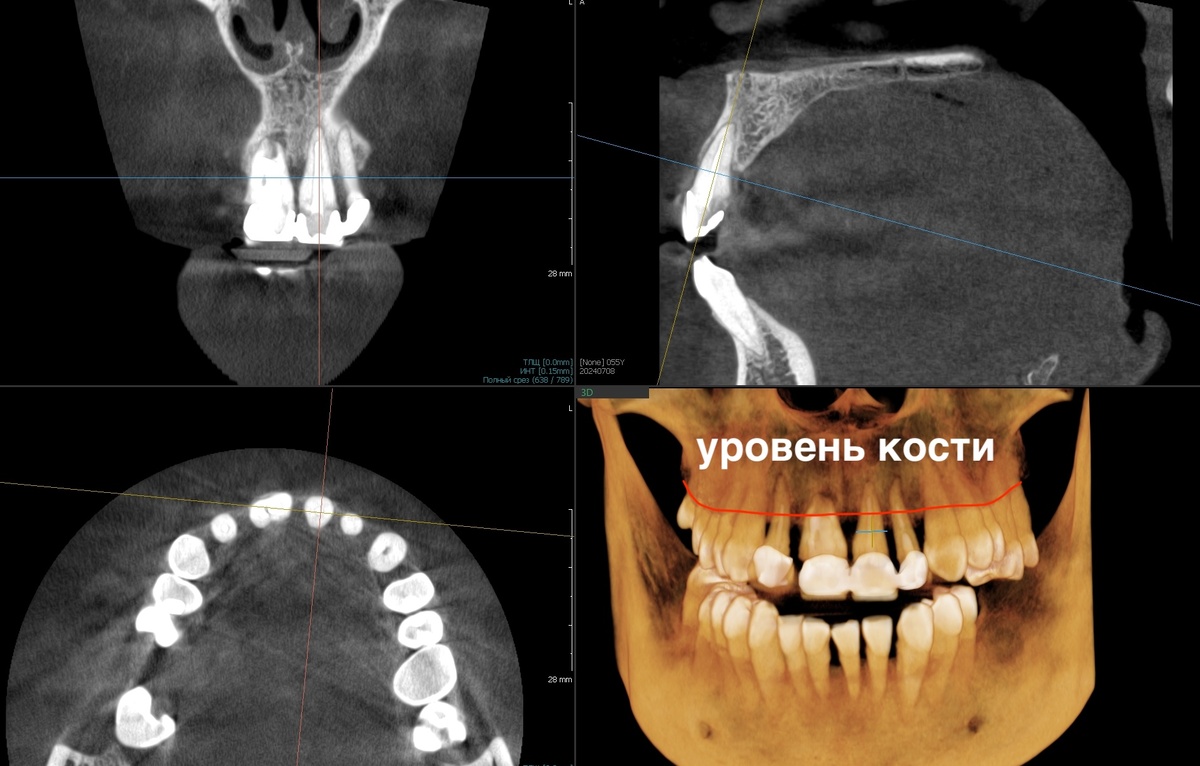

Изучили снимки и всё подтвердилось. Запрос на верхнюю челюсть.

-2

Пародонтит тяжёлой степени тяжести, хронический. Генерализованный.

Со своей стороны (а я пародонтолог), могу сказать, что с такими зубами человека оставить можно, можно их попридержать. Но - пародонтит никуда не денется, усмирить его при тяжёлой степени тяжести не выйдет стабильно и насовсем. Домашняя гигиена не покроет потребности по уходу за "тяжёлым пародонтитом", кость продолжит убывать.

Коварный пародонтит - рентгенологическая картина выглядит гораздо хуже, чем визуальная

Верим снимку рентгенологическому, а не глазам своим.